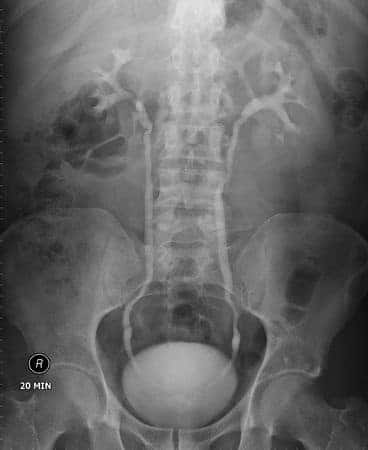

This case involves a fifty-three-year-old patient who presented to his urologist complaining of recent sexual dysfunction. He also complained of sleep disturbances, fatigue, and lower back pain. The urologist advised the patient that he may be suffering from low testosterone and would likely benefit from using AndroGel “trt,” or therapeutic testosterone cream. The physician only performed a physical exam on the patient but neglected to screen his blood for a baseline PSA value. Three months later, the patient returned with reports of improved sexual function but now complained of new urinary symptoms associated with occasional blood in the urine. Subsequently, the patient was found to have advanced prostate cancer.

It is widely accepted in the medical community that patients treated with androgens may be at increased risk for prostate cancer and it is of utmost importance to evaluate patients for possible prostate cancer prior to initiating and during treatment with androgen therapy.